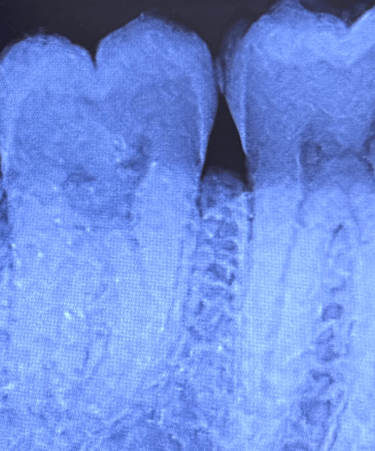

La radiografia endorale è un esame diagnostico che consente di ottenere un’immagine dettagliata di uno o più denti (fino a tre). Si tratta di una procedura minimamente invasiva, sicura e priva di rischi per il paziente.

Questa tecnica viene impiegata per l’analisi mirata di un dente o di un gruppo ristretto di denti, risultando fondamentale per una diagnosi accurata e per il monitoraggio dell’efficacia del trattamento. L’esame si avvale di pellicole o sensori digitali posizionati all’interno del cavo orale e mantenuti in sede da appositi centratori.

Status endorale